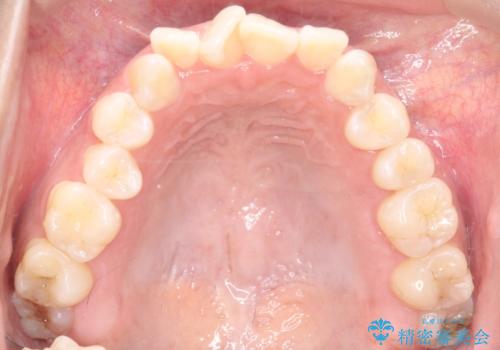

- 治療計画

治療では、審美ワイヤーを使用し、目立ちにくく配慮しながら矯正を進めました。上顎にリンガルアーチと矯正用アンカースクリューを用いて臼歯部を安定的に遠心移動させ、歯列全体のスペースを確保しました。その後、回転していた前歯を正しい位置に配列し、全体的な歯並びの改善を行いました。治療中は、装置の適切な管理と口腔衛生を徹底することが重要でした。結果として、見た目だけでなく機能的にも優れた歯列を実現することができ、患者様にもご満足いただけました。